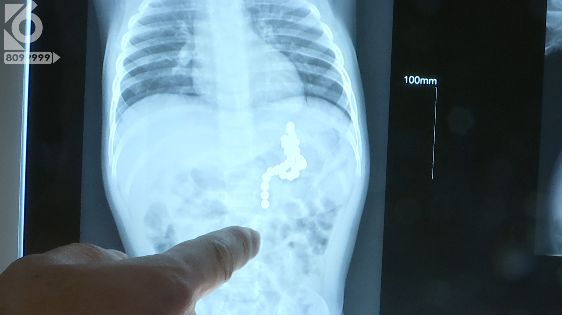

昆明市儿童医院 新生儿科主任 白强:“小孩子当时来的时候情况还可以,家长基本不知道什么时候吃进去的磁力珠,我们看这些片子上这些磁力珠的影像主要是在胃这个位置,所以想争取能不能先通过胃镜把磁力珠取出来。”

据了解,医生通过胃镜手术从月月的胃中取出了34颗磁力珠。

但术后复查的时候医生却发现,月月的小肠中还有两颗。医生又立即为她安排手术,在手术中医生发现,磁力珠在胃肠道内停留的位置处已经出现了溃烂。

昆明市儿童医院 新生儿科主任 白强:“第一次吃进了两颗,后面又吃进了三十多颗,所以在手术当中可以看到,空肠上端和胃吸在一起,穿孔那个位置是在空肠和胃那个位置。”

据了解,医生从小月月的腹中一共取出了36颗磁力珠,是医院截止目前,误食异物数量最多的患者。而据月月的家长介绍,月月有一个三岁的哥哥,被误食的磁力珠都是给哥哥玩的,他们也不清楚月月是什么时候把磁力珠吃到肚子里的。不过,还算发现及时,没有引起更大的危险。